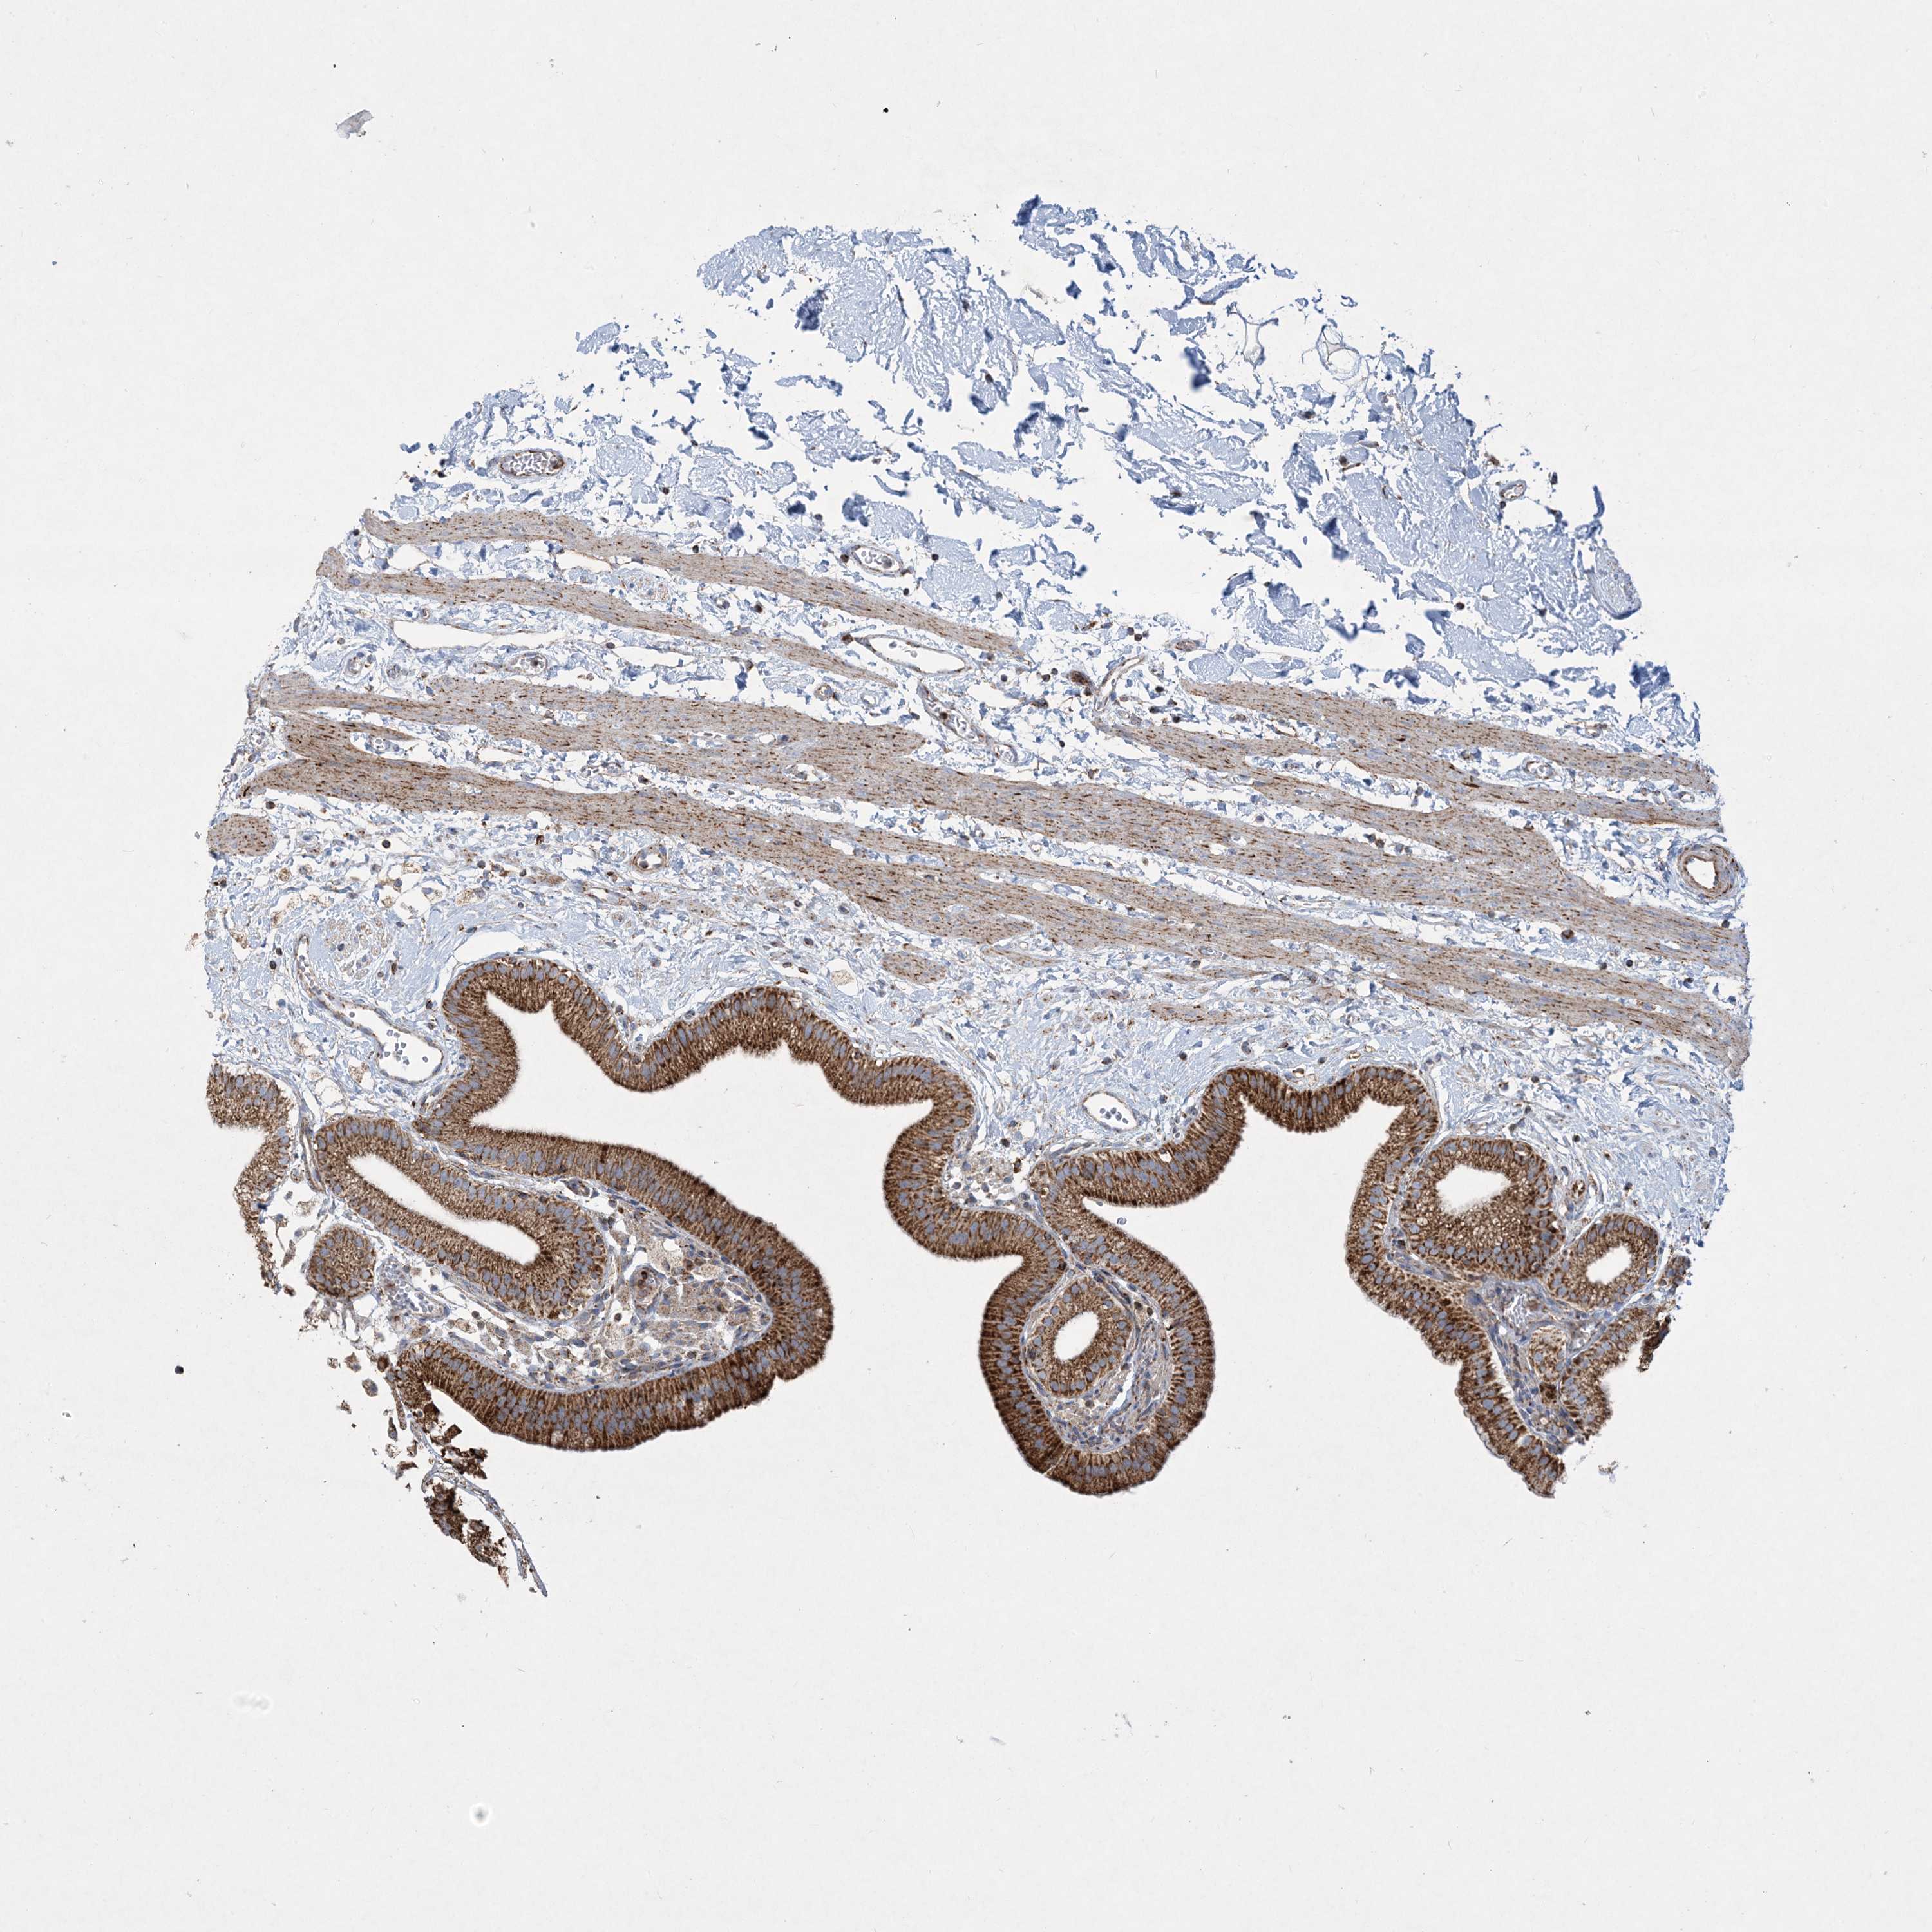

BEND4